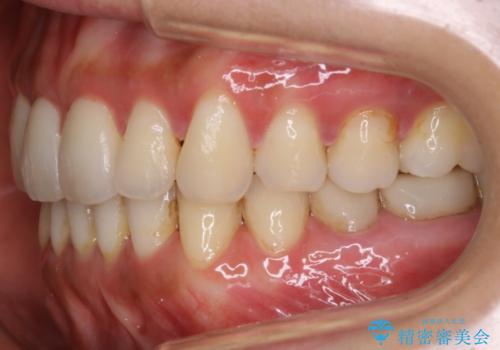

- 歯のガタつきによる見栄えや清掃困難を主訴にご来院されました。

左側の噛み合わせは上の歯が前方に寄ってきてしまっていることが原因のズレがありました。

ガタつき自体は歯列の幅の拡大やディスキング(IPR)でほとんど解消可能でしたが、噛み合わせのズレは歯の移動が必要だったため、左上にマイクロインプラントを使用し噛み合わせの改善とガタつきの解消を同時に進めるという方針をとりました。